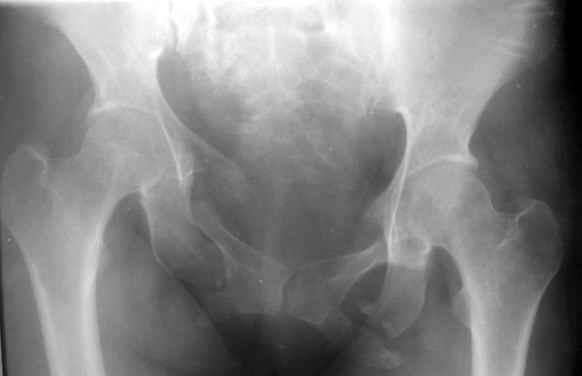

Застарелая деформация таза

Вопрос Уральскому Пельвиоцентру: через год после травмы, довольно симпатичная женщина, болей нет, только ходит призрамывая на правую ногу и сидит криво,

мышечная ассиметрия практически не выражена, хотя слабость справа есть. Легко компенсируется подкладкой стельки 1,5 см с выраженным клиническим эффектом. Посылаю снимки с вопросом - можно ли устранить деформацию в Вашем аппарате, если можно - то поподробнее. Снимки с разницей во времени почти 1 год. Жду ответа как соловей лета. ЛАФ.